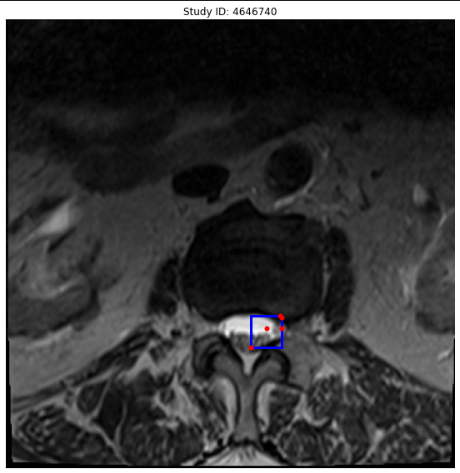

Faster R-CNN w/ ResNet50 epoch : 30 optim : SGD